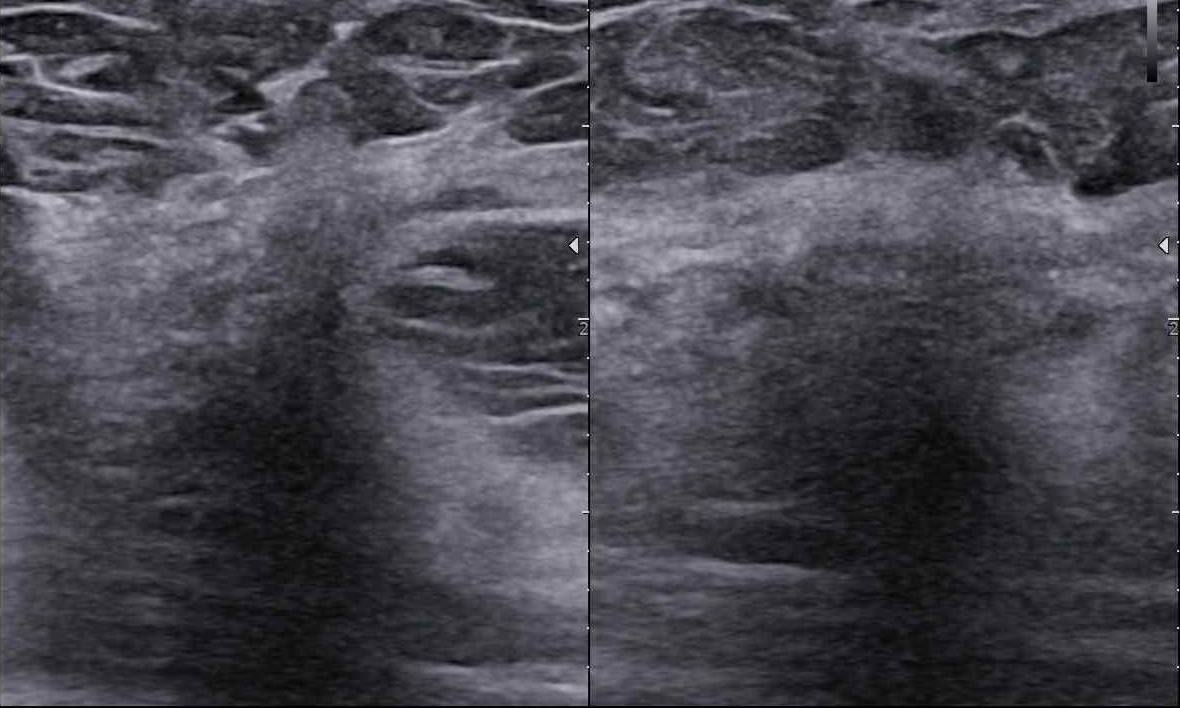

Czy podział BIRADS 4 ma sens? Jak radzić sobie z BIRADS 4a, b, c? Morfologiczne wskazówki